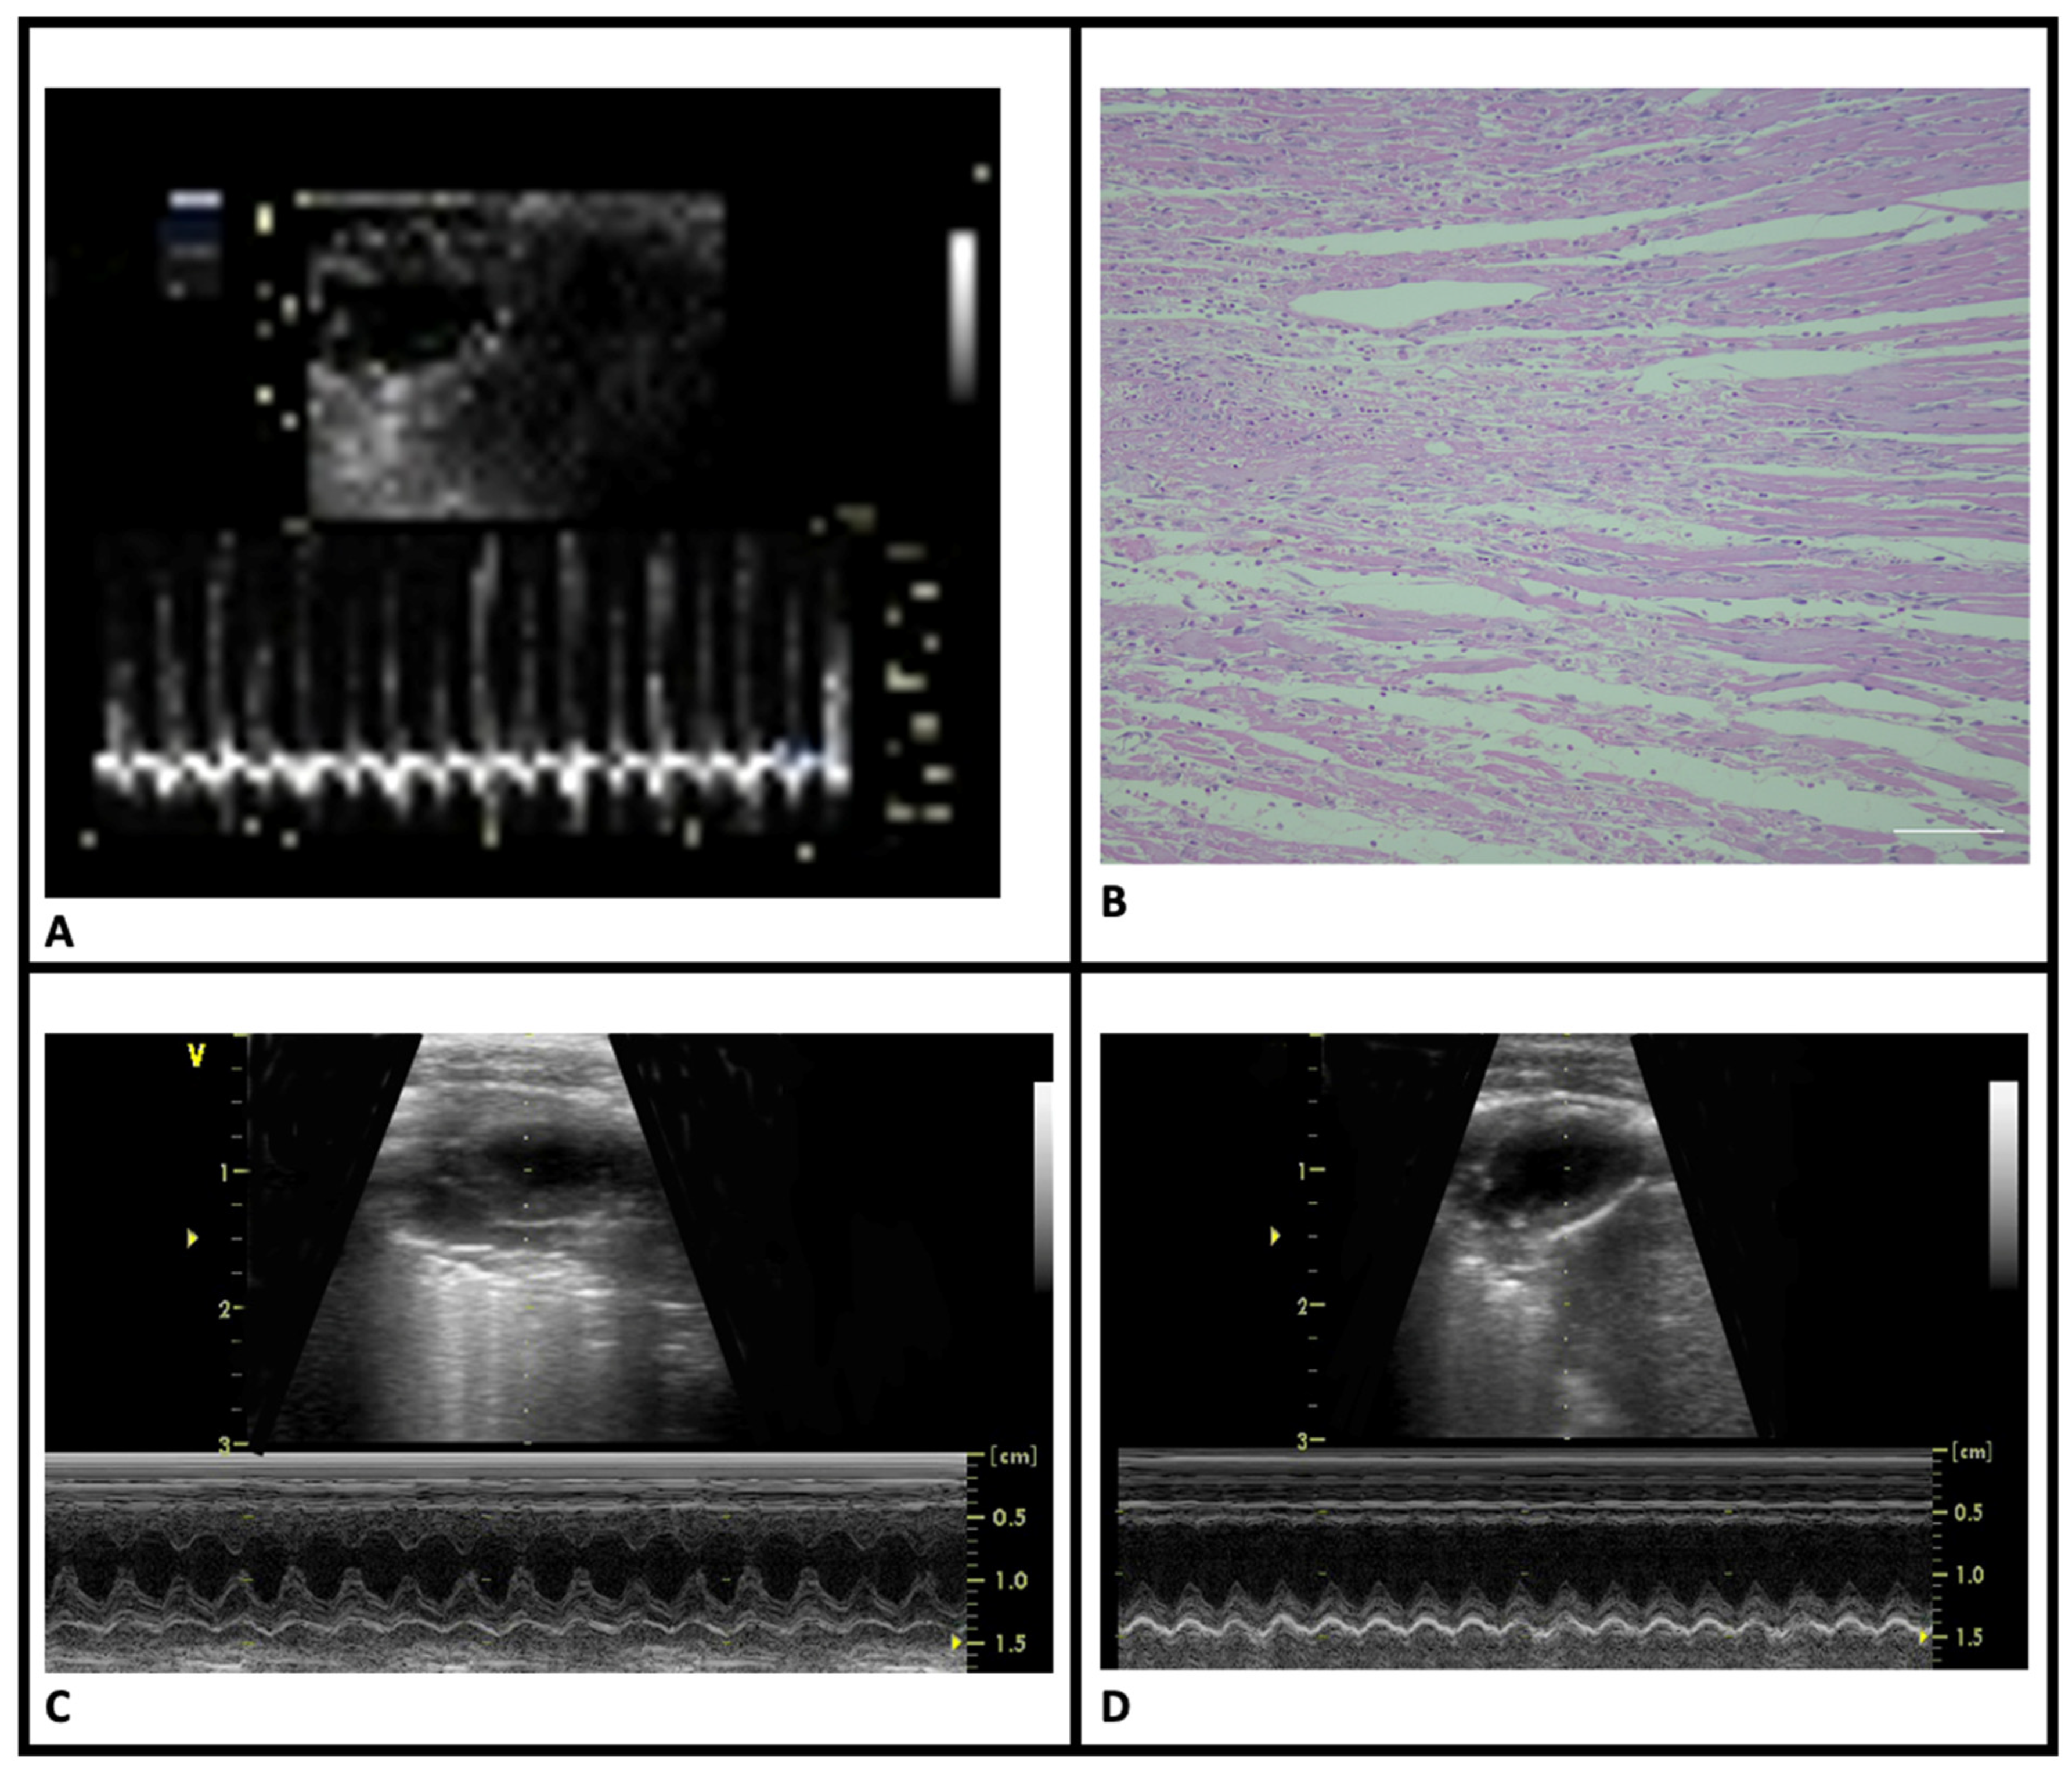

2.5. Evaluation of Cardiac Function

- Mercanoğlu, G.O.; Pamukçu, B.; Safran, N.; Mercanoğlu, F.; Fici, F.; Güngör, M. Nebivolol prevents remodeling in a rat myocardial infarction model: An echocardiographic study. Anadolu Kardiyol. Derg. 2010, 10, 18–27. [Google Scholar] [CrossRef]

- Mercanoglu, G.; Safran, N.; Ahishali, B.; Uzun, H.; Yalcin, A.; Mercanoglu, F. Nitric oxide mediated effects of nebivolol in myocardial infarction: The source of nitric oxide. Eur. Rev. Med. Pharmacol. Sci. 2015, 19, 4872–4889. [Google Scholar]

- Mercanoglu, G.; Safran, N.; Gungor, M.; Pamukcu, B.; Uzun, H.; Sezgin, C.; Mercanoglu, F.; Fici, F. The effects of nebivolol on apoptosis in a rat infarct model. Circ. J. 2008, 72, 660–670. [Google Scholar] [CrossRef] [PubMed]

| LVEDd (cm) | 0.63 ± 0.09 | 0.65 ± 0.07 | 0.60 ± 0.06 | 0.62 ± 0.04 |

| LVEDv (mL) | 0.69 ± 0.04 | 0.79 ± 0.06 # | 0.73 ± 0.12 | 0.72 ± 0.09 |

| EF (%) | 70.17 ± 6.20 | 58.17 ± 7.90 # | 66.17 ± 3.98 #,& | 64.28 ± 2.18 #,& |

| CO (mL/min) | 756 ± 269 | 724 ± 210 # | 762 ± 214 & | 760 ± 236 & |